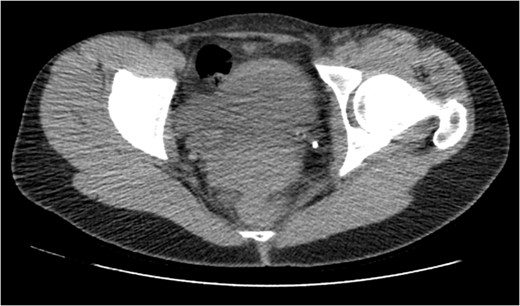

On Day 9 since presentation a CT IVU was repeated. This showed the stent in the left ureter to be in situ with no further leakage from the known rupture.

On table Pyelogram confirmed intact left collecting system and ureter.